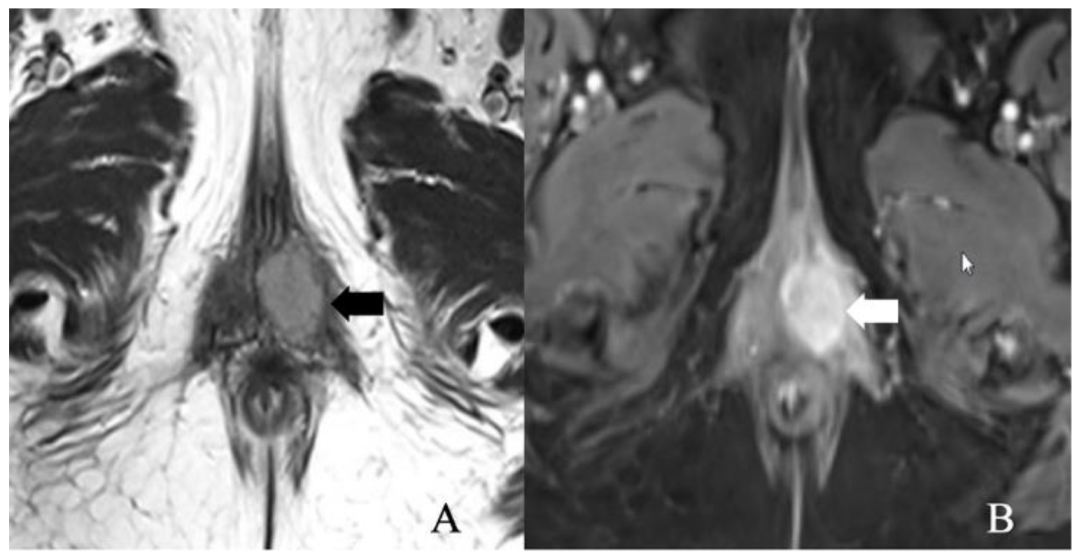

5.3. Stage III

5.4. Stage IV